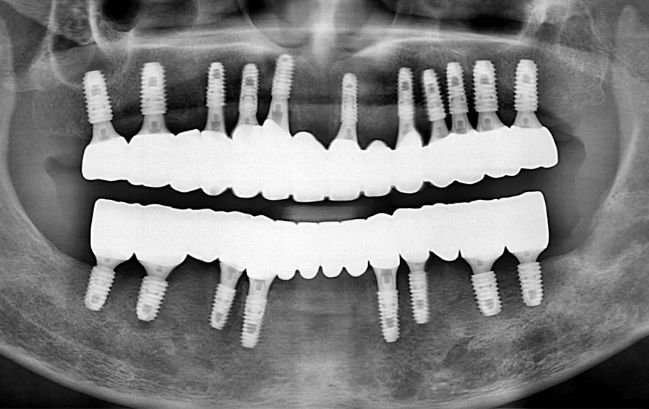

50대 남성, 원데이 수면 전체 임플란트 19개 식립